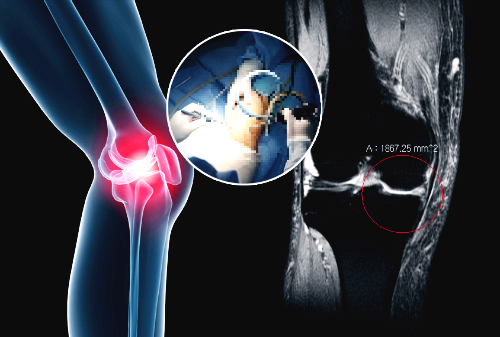

골관절염은 연골에 손상이 가해지면서 관절의 간격이 줄어들고 뼈가 서로 맞닿아 통증을 동반하는 질병입니다. 콘드로이친은 질병과 외부 충격으로부터 체내의 조직을 안전하게 보호하고 동시에 조직 표면에 가해지는 충격 등을 이겨낼 수 있도록 탄성을 주는 프로테오글리칸(Proteoglycan)이라는 물질의 생성을 돕게 됩니다. 때문에 콘드로이친은 특히 골관절염에 효과가 있습니다.

콘드로이틴황산염은 연골 구성 성분의 하나이고 연골세포를 자극해 연골조직을 정상적으로 복원하는데 효능이 있다고 알려져 있습니다. 특히 외부 자극에 의해 문제가 되는 TNF-알파 등 사이토카인의 작용을 억제하는 역할을 합니다. 그리고 지속적인 염증 유발 및 연골 파괴 유발 사이토카인을 감소시켜 관절 내 염증 및 통증반응 그리고 연골파괴를 막아주는데 도움을 줍니다.

콘드로이친은 연골에 보습 및 탄력을 공급하려 상처 난 연골을 정상적으로 재생시키는 효과가 있습니다. 콘드로이친을 섭취하게 되면 무릎이나 허리 등의 관절염으로 인한 통증을 완화시킬 수 있습니다.

콘드로이친은 글루코사민과 같이 연골 성분의 일부로써 연골, 힘줄, 뼈, 각막 등의 신체 결합 주위에 널리 퍼져 있습니다. 관절 연골에 필요한 영양을 공급하고 연골을 분해하는 효소를 억제함으로써 관절 건강에 도움을 줍니다.

그렇지만 이미 연골의 손상이 심각하다면 관절 영양제를 먹어도 손상된 연골을 복구할 수는 없습니다. 다만 관절의 손상 속도를 지연시키는 보조제 역할 정도로 활용할 수 있습니다.